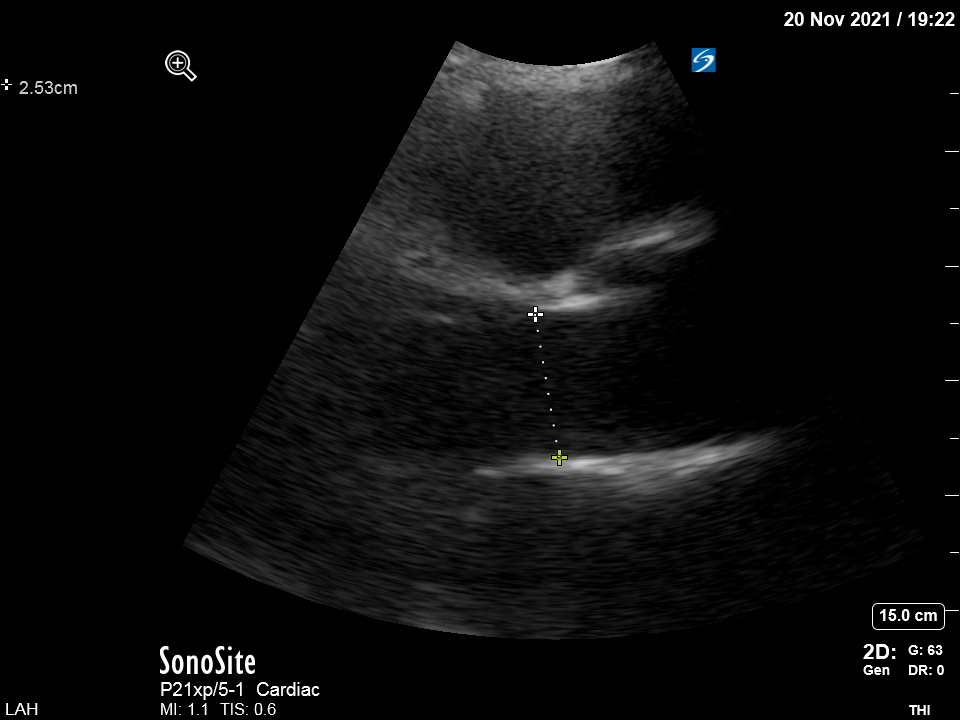

My next step was to measure LVOT VTI. It was around 9 cm (mean value of several beats since pt was in A fib). Nl value: 18-22. The LVOT from a zoomed view:

and the LVOT diameter was measured 2.53 cm. Sounds large but it fits w patient's size. Don't assign "2 cm" in every LVOT diameter because sometimes you will make big mistakes

I measured CO 4.5 l/m. If the diameter was blindly set at 2 cm, the CO would be off by 38%...